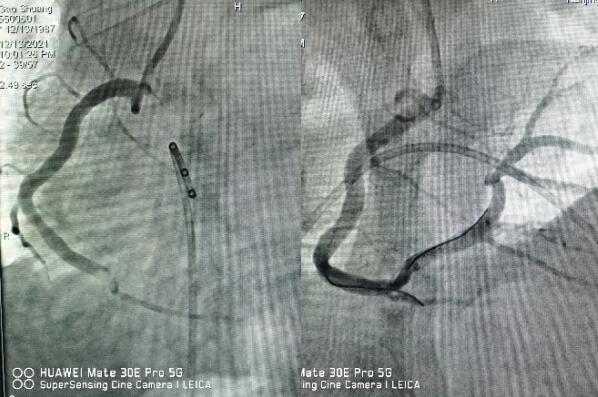

醫(yī)生立即予以搶救,并第一時間通知心內(nèi)科值班醫(yī)師,緊急啟動綠色通道,全院相關(guān)科室全力配合,心內(nèi)科介入團(tuán)隊(duì)分工明確,迅速啟動導(dǎo)管室。因患者心梗后并發(fā)嚴(yán)重心律失常,為了安全起見,造影前植入臨時起搏器,造影提示右冠狀動脈急性完全閉塞,并成功開通血管,患者胸痛即刻緩解,目前正在康復(fù)過程中。